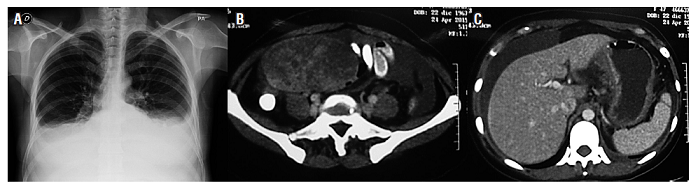

Una tomografía axial computarizada (TAC) de abdomen con contraste (24 de abril del 2015) demostró un leve aumento en el número de ganglios retroperitoneales. El útero estaba aumentado de tamaño con presencia de miomas y masa anexial derecha heterogénea de 110 x 79 x 71 mm de contornos lisos, bien definida y sólida; se encontraba una moderada cantidad de líquido libre en la cavidad; la pared gástrica corporal estaba engrosada; y el peritoneo era nodular (Figura 1).

La paciente fue valorada por gastroenterología y ginecología con diagnóstico de tumor de Krukenberg. Se decide llevar a laparoscopia el día 12 de junio del 2015 y se encontró líquido ascítico en cantidad de 400 mL, múltiples implantes peritoneales en el peritoneo pélvico, cúpulas diafragmáticas, epiplón, masa ovárica derecha de 10 cm de diámetro y un tumor gástrico en la región corporal. El índice de carcinomatosis peritoneal (ICP) fue de 24. La citología de líquido ascítico resultó negativo para malignidad.

Es valorada por oncología. Se inicia la quimioterapia con capecitabina (1,5 g vía oral, cada 12 horas, del día 1 al 14) y cisplatino (125 mg intravenoso [IV], única dosis) desde el 7 de julio del 2015. Completó 8 ciclos. En sus controles periódicos se detectó un alivio clínico importante, recuperación de su estado funcional y nutricional, mejoría en las cifras de sus marcadores bioquímicos como el ACE, CA 19-9 y del CA-125. El seguimiento mostró desaparición de la ascitis y aumento de la masa ovárica. Por este motivo, se le propuso una nueva laparoscopia, que se realizó el 12 de noviembre del 2015 con el hallazgo de un ICP de 8, sin implantes peritoneales en cúpulas diafragmáticas, estómago móvil sin adherencias y compromiso metastásico del ovario derecho. No hay líquido libre en cavidad abdominal (Figura 2).